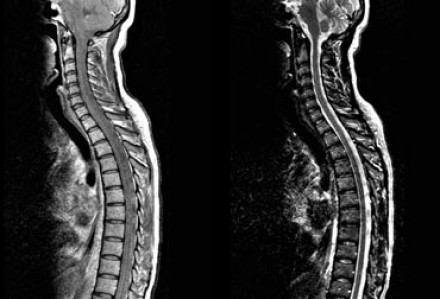

圖片八

該患者的脊髓是正常的。血管炎或缺血性疾病患者的脊髓通常是正常的,而90%以上的MS患者的脊髓MRI成像都會發(fā)現(xiàn)異常。如果很難區(qū)分老年患者的白質(zhì)損傷病灶是血管源性的還是MS,則對該患者行MR成像將非常有助于鑒別診斷。

圖片九

現(xiàn)狀我們回過頭來第一個案例,很明顯這是一個血管性疾病患者,深部白質(zhì)中有廣泛病變,但U形纖維和胼胝體未被累及。

缺血性白質(zhì)損傷病灶表現(xiàn)為腔隙性梗塞、分水嶺梗塞或深部白質(zhì)彌漫性高密度病變。

腔隙性梗塞是由于穿透髓質(zhì)的小動脈發(fā)生硬化造成的。分水嶺梗塞是由于更大的血管發(fā)生動脈粥樣硬化造成的,如頸動脈阻塞或灌注不足。50歲以上的患者中,發(fā)生大腦動脈粥樣硬化性病變者高達50%。可見于血壓正常的患者,但高血壓患者更常見。